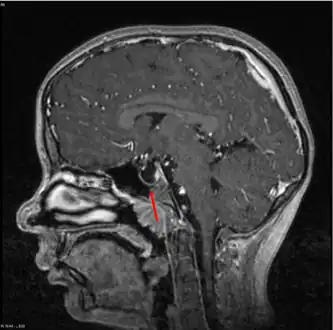

Empty sella- MRI Scan of the brain, sagittal T2-weighted

Empty sella in MRI